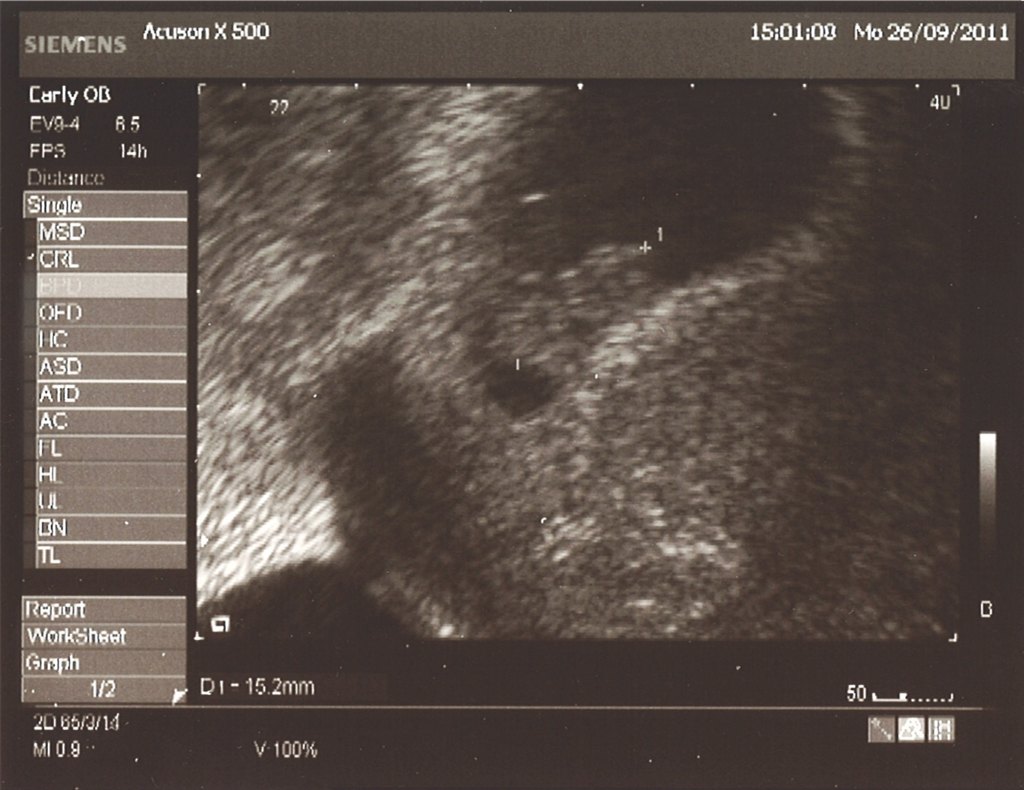

Så var vi nede og se baby igen

Har lagt billedet ind i scanningsbilleder men i skal da også lige have det herinde

Man kan helt se ansigtet. Fantastisk oplevelse

baby er 15 mm

SÅ det passer perfekt

Fantastisk og dejligt billede  Det kan jo slet ikke beskrives når man ser hjertet slå derud af...